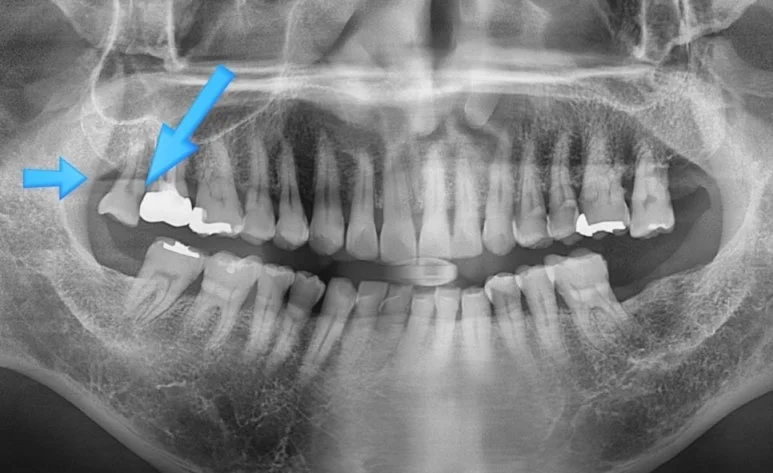

오산 치아진단 엑스레이 얼마나 꼼꼼히 하느냐가 중요합니다. 안녕하세요 서울버팀치과 엄용국원장입니다. “치과에 방문해 치료를 받았습니다.” 하지만 치과에서 치료를 받았다는 사실만으로 항상 적절한 치료가 이루어졌다고 단정하기는 어렵습니다. 정확한 진단을 위해서는 엑스레이 촬영...